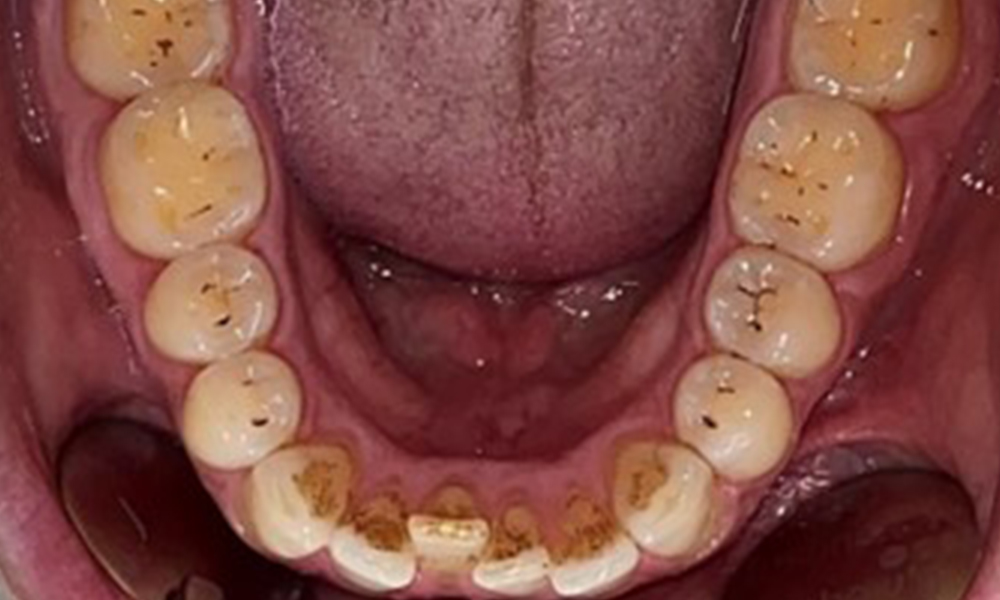

Няма патологични екстраорални резултати. По време на интраоралния преглед се установи кафеникаво оцветяване в близост до кератинизираната гингива и при прехода към подвижната лигавица (фиг. 2), което може да се отдаде на консумацията на никотин. В областта на небцето, особено в близост до небцовите повърхности на максиларните молари, се наблюдават белезникави лезии на лигавицата, които показват повишена кератинизация и също могат да се припишат на консумацията на никотин. Езикът е покрит с бяло-кафеникаво покритие, което може да се отстрани.

Пациентът има пълно съзъбие с общо 28 зъба. Налице са забележими ерозии и атриции. (Фиг. 4, Фиг. 5). Поради бруксизъм пациентът е носил шина с коригиран блок на захапката през нощта в продължение на много години. Ерозиите са причинени от продължителна консумация на изотонични напитки. Не сe наблюдава загуба на пародонтална кост или активни кариозни лезии.